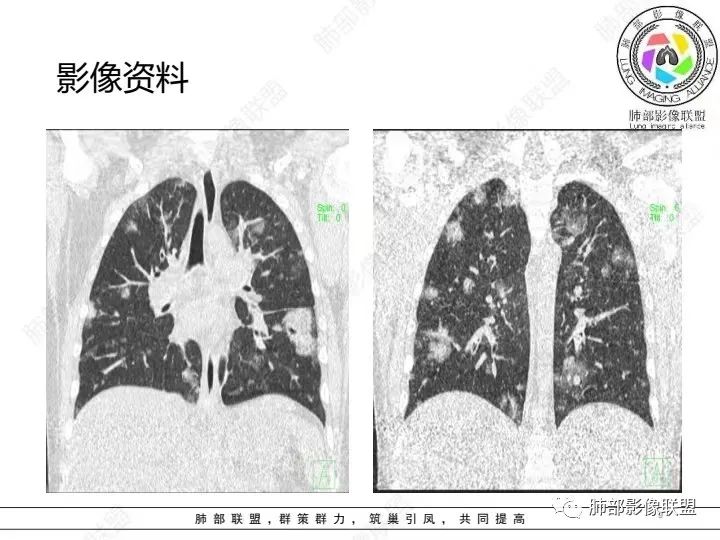

2.影像上肺多发混合密度片影,随机分布,胸膜下分布优势,病灶边界大多隐约可辨,偏柔和,动脉血管影穿行,未见钙化、液化空洞、或明确气囊影,未见树芽征。

3.影像方面:双肺多发病灶,随机分布,且有相当部分沿胸膜下,是可以符合血流感染的。

1.外围分布,胸膜下为主,两肺弥漫结节或胸膜下楔形影,边界清,周围伴有GGO

2.反晕征:往往紧贴胸膜,并且胸膜侧无环,周围GGO